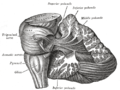

Cerebellum sag.jpg

Figure 1b: MRI image showing a mid- sagittal view of the human brain, with the cerebellum in purple.

The cerebellum is located in the inferior posterior portion of the head (the hindbrain), directly dorsal to the pons, and inferior to the occipital lobe (Figs. 1 and 3). Because of its large number of tiny granule cells, the cerebellum contains more than 50% of all neurons in the brain, but it only takes up 10% of total brain volume. The cerebellum receives nearly 200 million input fibers; in contrast, the optic nerve is composed of a mere one million fibers.